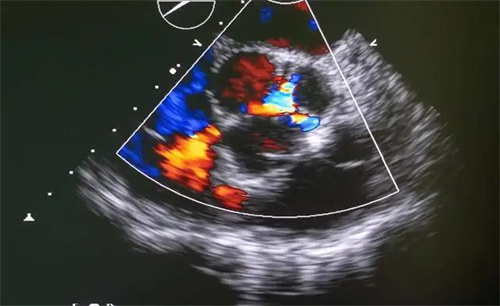

大量研究提示:在结构性心脏正常、心脏彩超和心功能都合格的前提下,每天少量早搏(如 Holter 监测<1000次/天)多为良性,多数人一辈子带着也没问题。